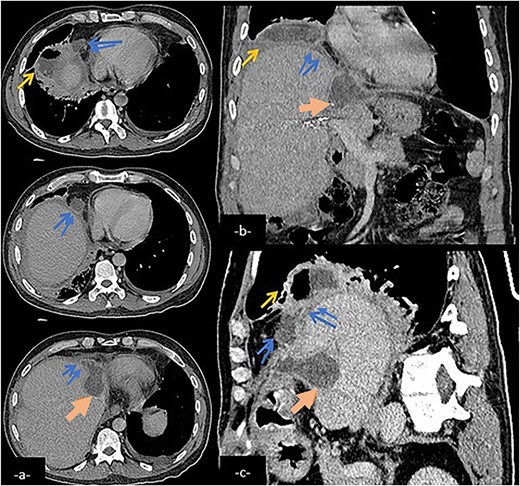

Abdominal CT scan in axial (a), coronal (b), and sagittal (c) reconstruction showing a biliary collection (large arrow) in the left hepatic lobe communicating with a subphenic and pleural collections with possible connexion with lower right airways (arrow) via a fistulary tract (double arrow).

CT is the most frequently utilized imaging method to properly evaluate the upper abdomen and chest. It often reveal a subphrenic fluid collection, indicative of a biloma, right-sided pleural effusion, lacerations of the liver dome, diaphragm disruption, or dilated bile ducts in the presence of biliary obstruction [10]. However, the fistula itself is rarely visualized on CT.